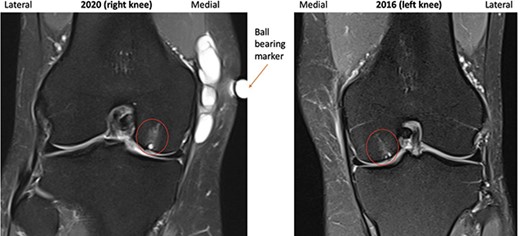

Clinical examination revealed a firm 5 × 5-cm lump, located above the medial joint line and behind the medial collateral ligament (MCL). The left knee was otherwise normal. X-rays showed ‘mild medial and patella-femoral OA’. Due to concerns that the lump was malignant, a Gadolinium-enhanced MRI scan was performed and illustrated a septated ganglion cyst, measuring 45 × 29 × 17 mm, without solid components or malignant features. A 2-mm wide articular cartilage defect was evident in the medial femoral condyle, which was associated with adjacent subchondral cyst formation. Subchondral cyst formation was also present under the medial patella facet associated with articular degeneration.

A repeat MRI was performed and reported ‘very similar’ appearances to the left knee, showing a septated ganglion originating from the postero-medial aspect of the joint and subchondral cyst formation with a pattern and location mirroring that which had involved the left knee (Figs 1–3). Reassured by these findings, the patient deferred surgery.

2016 and 2020 T2-weighted MRI in coronal plane with subchondral cyst circled medially.

Subchondral cyst formation associated with localized articular cartilage loss was evident in the weight-bearing portions of both medial femoral condyles and patellae, parts of the knee which are most commonly affected by articular cartilage loss in OA [6].